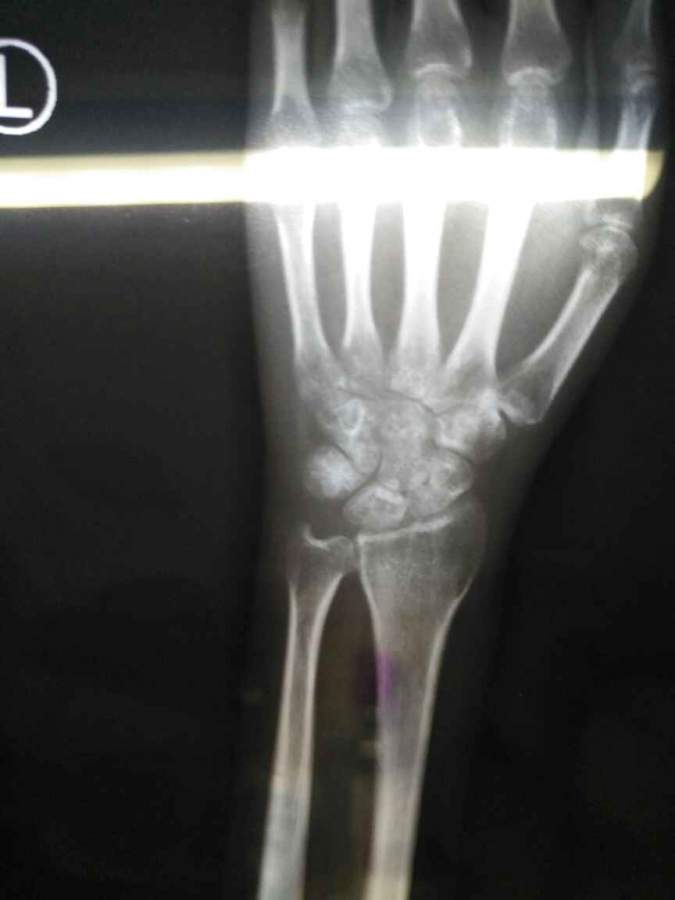

如题,能否帮我看一下图一手腕处的撕裂性骨折是指红线标记的位置吗?如果是的话,那图二算是恢复了吗? 发自小木虫Android客户端 |